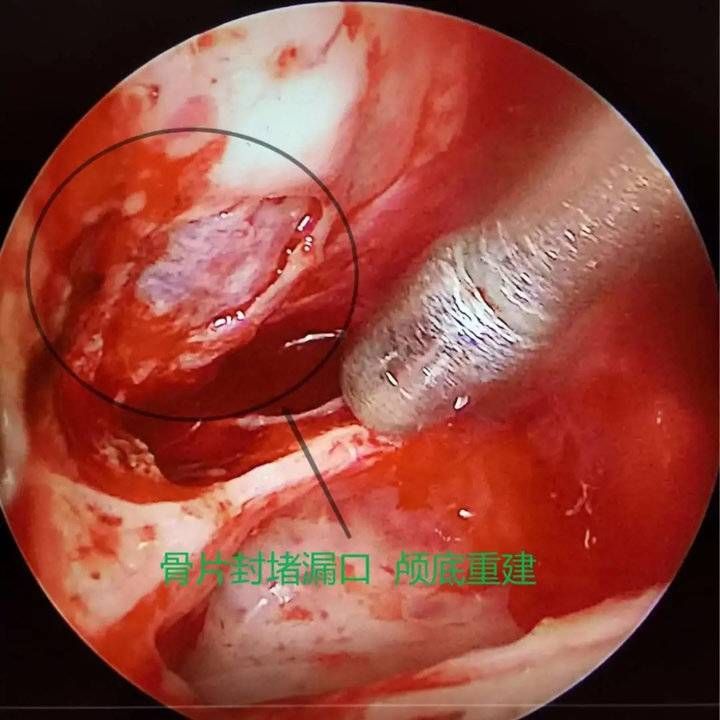

经呼吸科、麻醉科、耳鼻喉科及重症医学科评估后,8月4日,赵秋良主任团队为患者进行了鼻内镜下脑膜脑膨出切除+脑脊液修补+颅底重建手术。赵秋良主任介绍,这是全市首例鼻内镜下脑脊液修补手术,是鼻科鼻内镜微创手术里难度系数最高的四级手术之一,该手术充分利用人体自然腔道,全程在高清屏幕直视下完成,创伤小、愈后良好,术后并发症少,脑脊液修复的成功率高达90%。